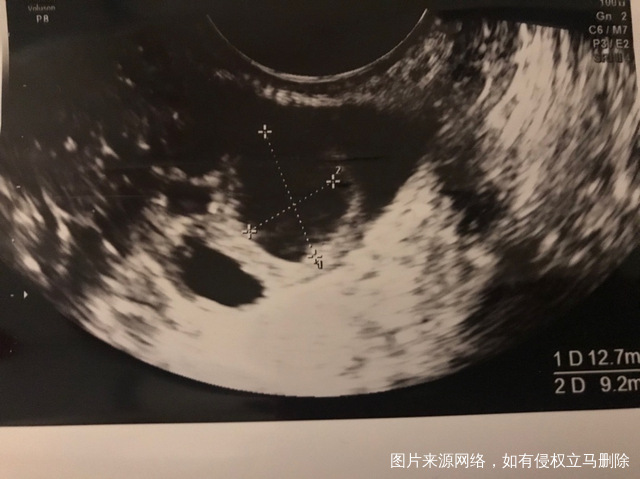

月经第三天发现有两个大卵泡见图一个12866